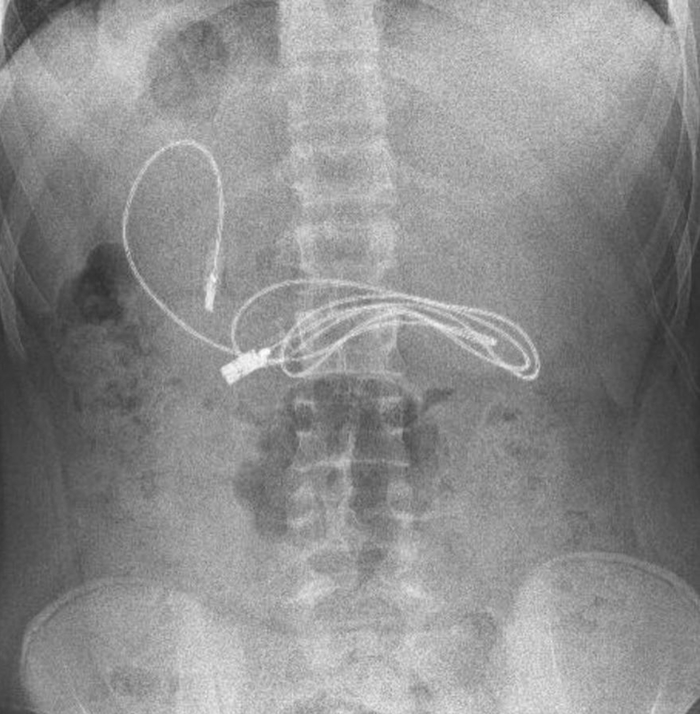

Çekilen röntgende midesinde bir metrelik şarj kablosu ve toka tespit edildi.

Ambulansla Fırat Üniversitesi (FÜ) Hastanesine sevk edilen çocuğun midesindeki şarj kablosu ve toka, Çocuk Gastroenteroloji Hepatoloji ve Beslenme Bilim Dalı Başkanı Prof. Dr. Yaşar Doğan ve ekibi tarafından gerçekleştirilen endoskopik operasyonla çıkarıldı.